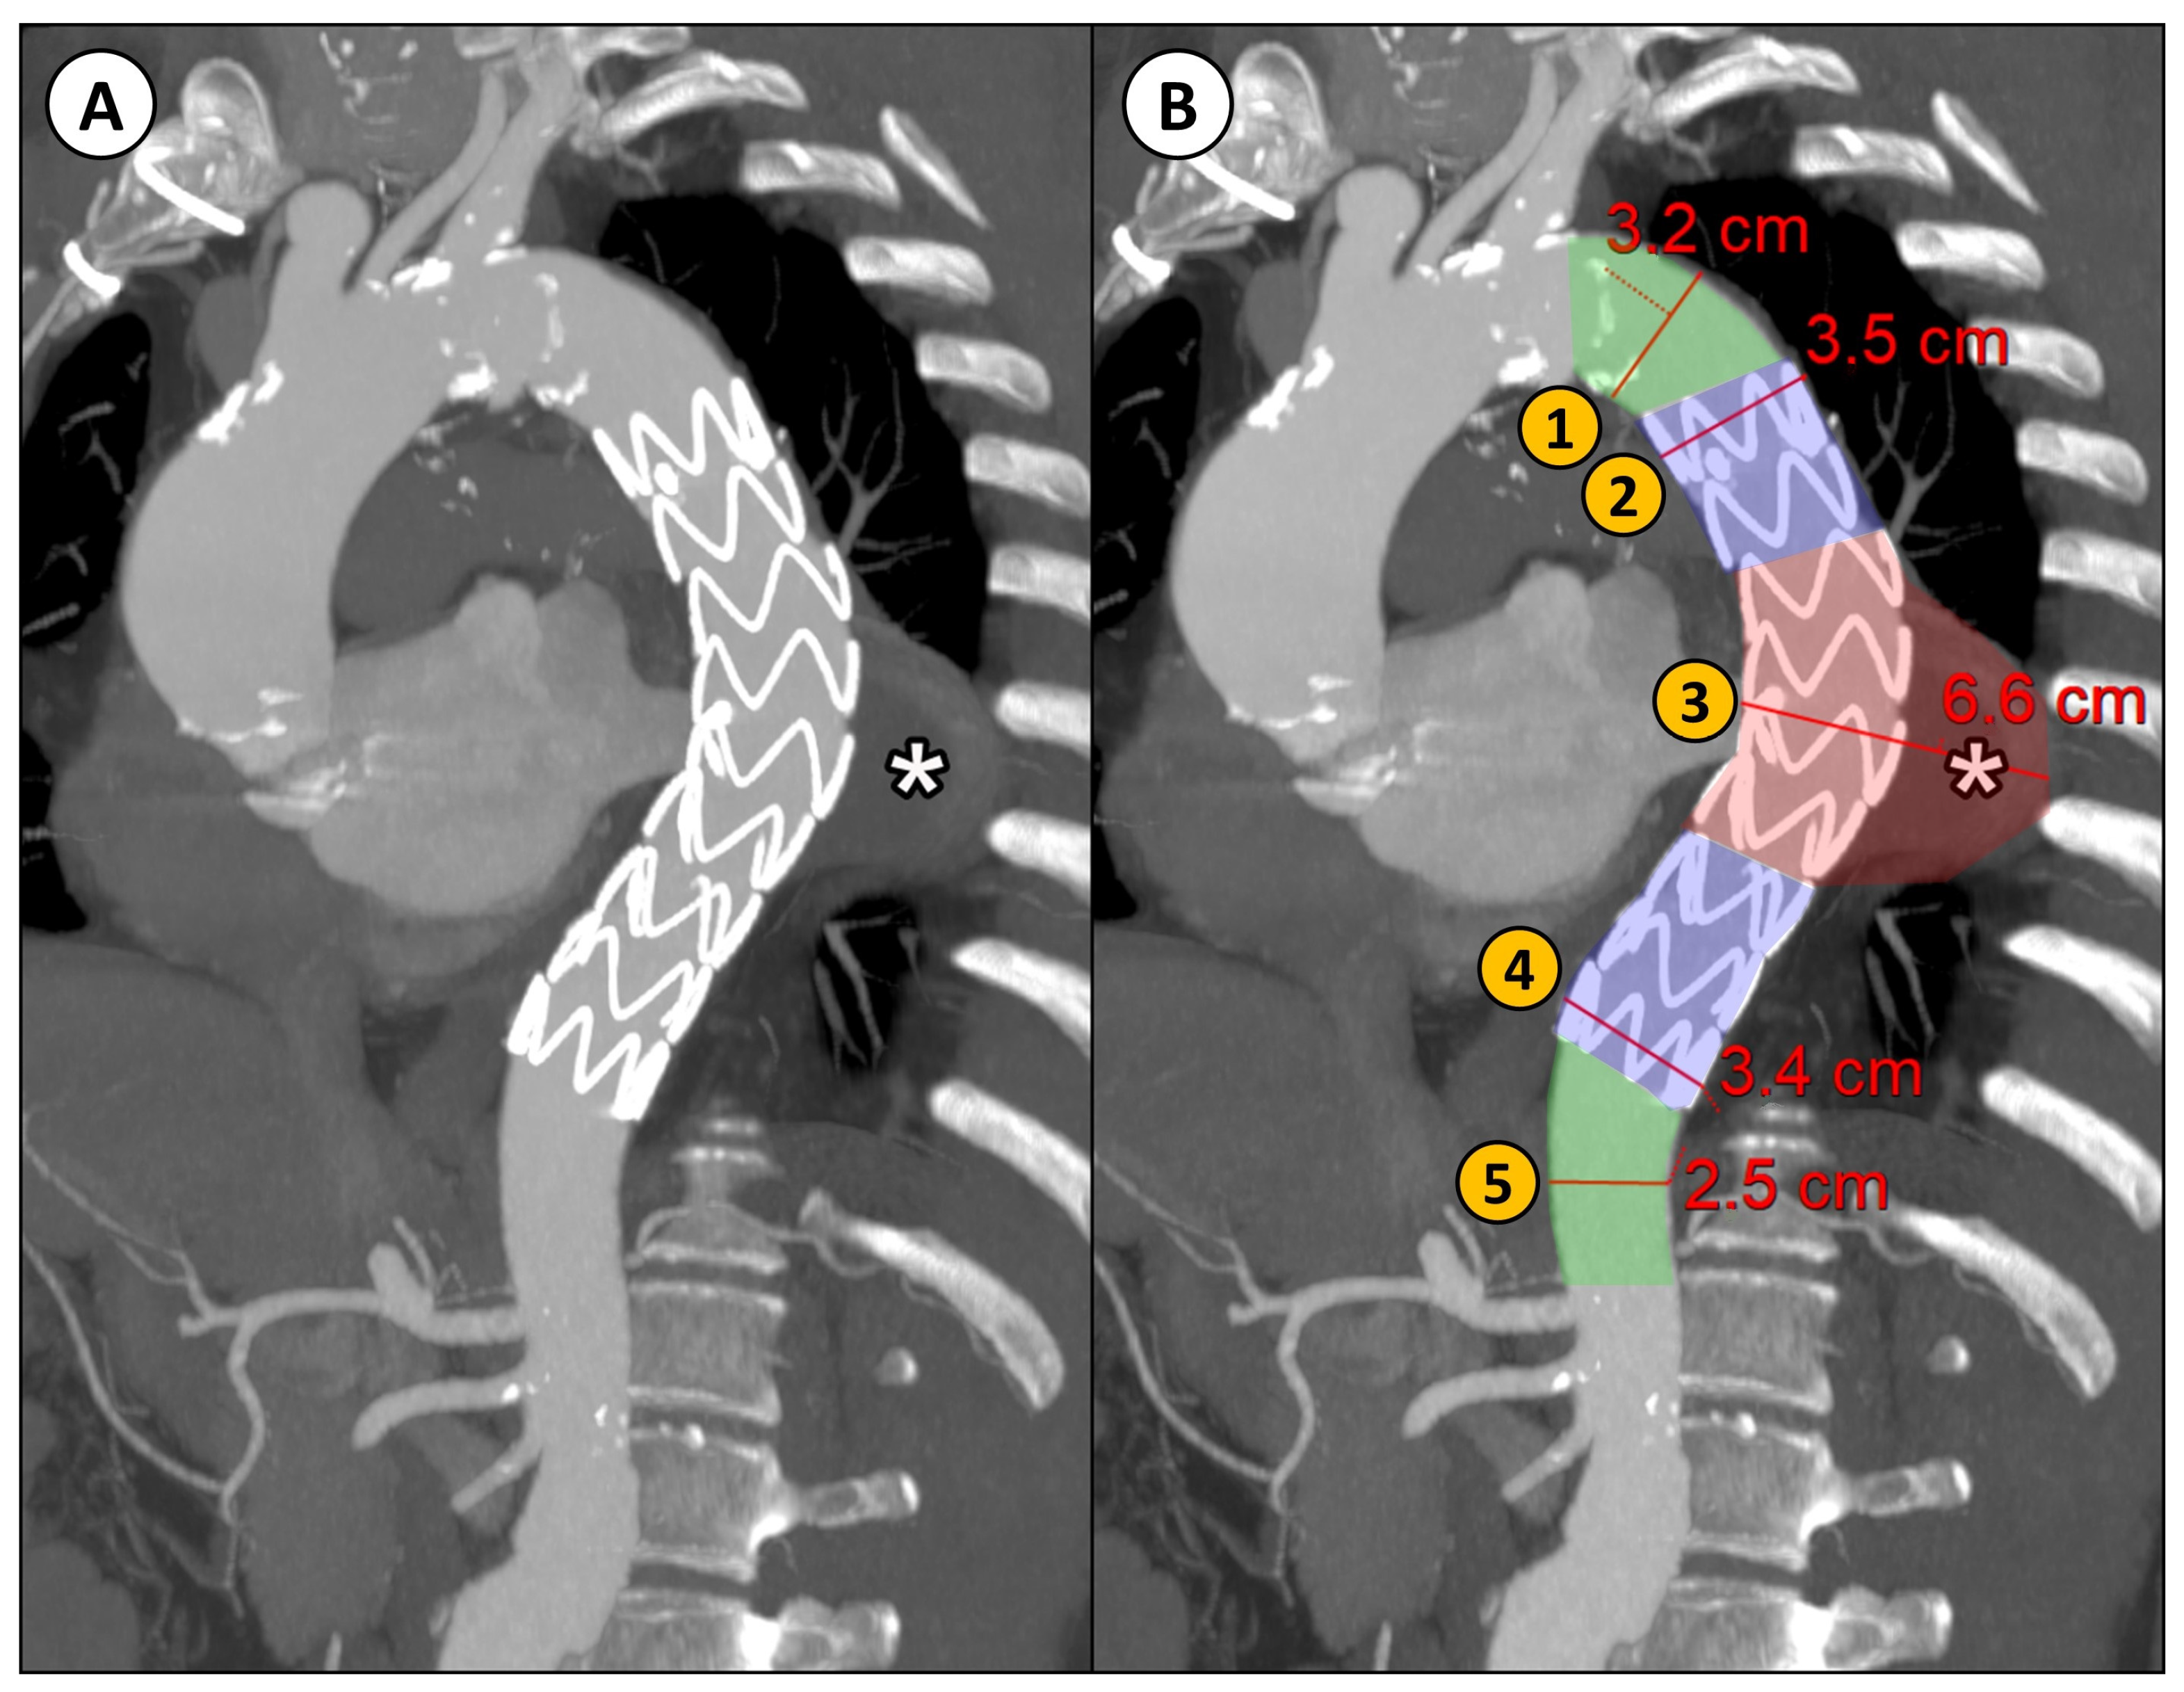

Descending thoracic aortic maximum diameters were taken by manual measurements with MPR reconstructions orthogonal to the aortic flow axis at 5 different regions relative to the stent graft into which the descending aorta was divided (Figure 1):

Figure 1.

(A) CTA parasagittal MPR with maximum intensity projection (MIP) reconstruction of the thoracic aorta in a patient with DTAA (*) treated with TEVAR; (B) an example of the manual diameter evaluation of the aorta at five different levels relative to the implanted stent graft: (1) proximal neck (native aorta between the origin of the left subclavian artery and the proximal landing zone of the stent graft); (2) proximal landing zone of the stent graft; (3) aneurysm; (4) distal landing zone of the stent graft; (5) distal neck (native aorta between the distal landing zone of the stent graft and the origin of the celiac trunk).

- Proximal neck (native aorta between the origin of the left subclavian artery and the proximal landing zone of the stent graft);

- Proximal landing zone of the stent graft;

- Aneurysm;

- Distal landing zone of the stent graft;

- Distal neck (native aorta between the distal landing zone of the stent graft and the origin of the celiac trunk).

The segmented aorta was then divided into the same 5 parts, as previously described for the diameter measurements (Figure 2).

Figure 2.

Descending thoracic aorta volume analysis with D2P software. (A) Segmentation of the aorta, the thrombus inside the aneurysm, and the stent graft. (B) Segmentation of the descending thoracic aorta relative to the position of the stent graft, defined as: (1) the native aorta proximal to the stent graft landing zone, (2) the proximal stent graft landing zone, (3) aneurysm, (4) distal stent graft landing zone, and (5) the native aorta distal to the stent graft landing zone.

An example of the two types of analysis is reported in Figure 4.

Figure 4.

Example of a patient case analyzed by both methods: the conventional manual measurement from CTA imaging using MPR reconstructions orthogonal to aortic flow axis (A) and the new volumetric analysis (B), both performed at discharge and at the 12 month follow-up (FU) after TEVAR. (1) Proximal Neck; (2) Proximal Landing Zone; (3) Aneurysm; (4) Distal Landing Zone; (5) Distal Neck.